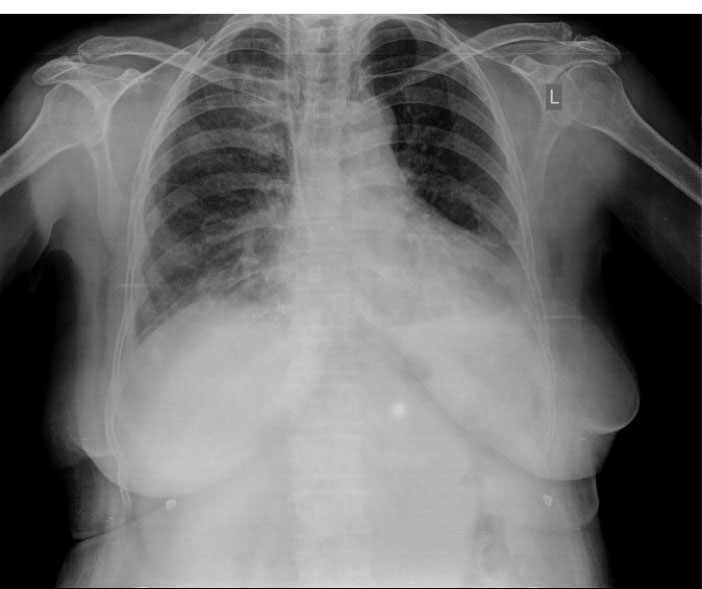

Three hours later, we noticed that she was pale and hypotensive. In physical examination, clear blood was seen inside the patient’s mouth but we did not find any bleeding signs in the nasal-gastric tube. Further, in the chest exam, she had diffuse rales over both lung areas, while there was no hemorrhagic site. Laboratory tests were performed and we found metabolic acidosis and drop of Hb from 13 to 7.5. With abdominal sonography, retroperitoneal hemorrhage was ruled out. Chest radiography exhibited bilateral alveolar infiltrates which was dominant in the right lung. A pulmonary computed tomography scan was done to rule out pneumonia, pulmonary edema, and pulmonary infarct (). With suspected cardiopulmonary edema underwent LAD involvement to roll out of acute mitral regurgitation, repeated echocardiography was done that revealed mild LV dysfunction with mild MR. During the diagnostic evaluations, management steps were started simultaneously, including eptifibatide infusion discontinuation, administration of pack cell, and Fresh Frozen Plasma (FFP). After three days, the patient was extubated but developed a mild right hemiparesis, though brain MRI was normal and ischemic encephalopathy was raised. The patient found worsening hypoxia and alveolar infiltrates were diffused. Six days later based on these clinical manifestations and evaluation results, we suspected the diagnosis of DAH and performed diagnostic bronchoscopy. This revealed distributed dark blood throughout the bronchial tree and displayed on serial bronchiolar lavage hemorrhagic return was increased, thus confirming the diagnosis DAH. shows a chest X-ray eight days later, which alveolar infiltration improved. The patient had hemoptysis for 2 weeks. Also, she had functional loss in daily living activity. For rehabilitation and function improvement, she was transferred to the subacute geriatric ward. One month later, the patient was discharged with a relatively good general condition. Now, after 4 years, the patient is symptom free and on re-catheterization all the stents were patent.

Figure 2.

Areas of consolidation, ground-glass, and normal in pulmonary computed topography scan.

Figure 3.

A chest X-ray eight days later shows improvement in alveolar infiltration.

It is generally considered safe to perform thrombolytic therapy if CPR is maintained for at least 10 minutes. However, there was no clear association between resuscitation duration and bleeding complications. 10 Meanwhile, when CPR was performed on this patient, no ribs were broken and as evident from the CXR images, there was no lung damage. Additionally, no clear correlation between CPR and DAH had been documented in the literature.11